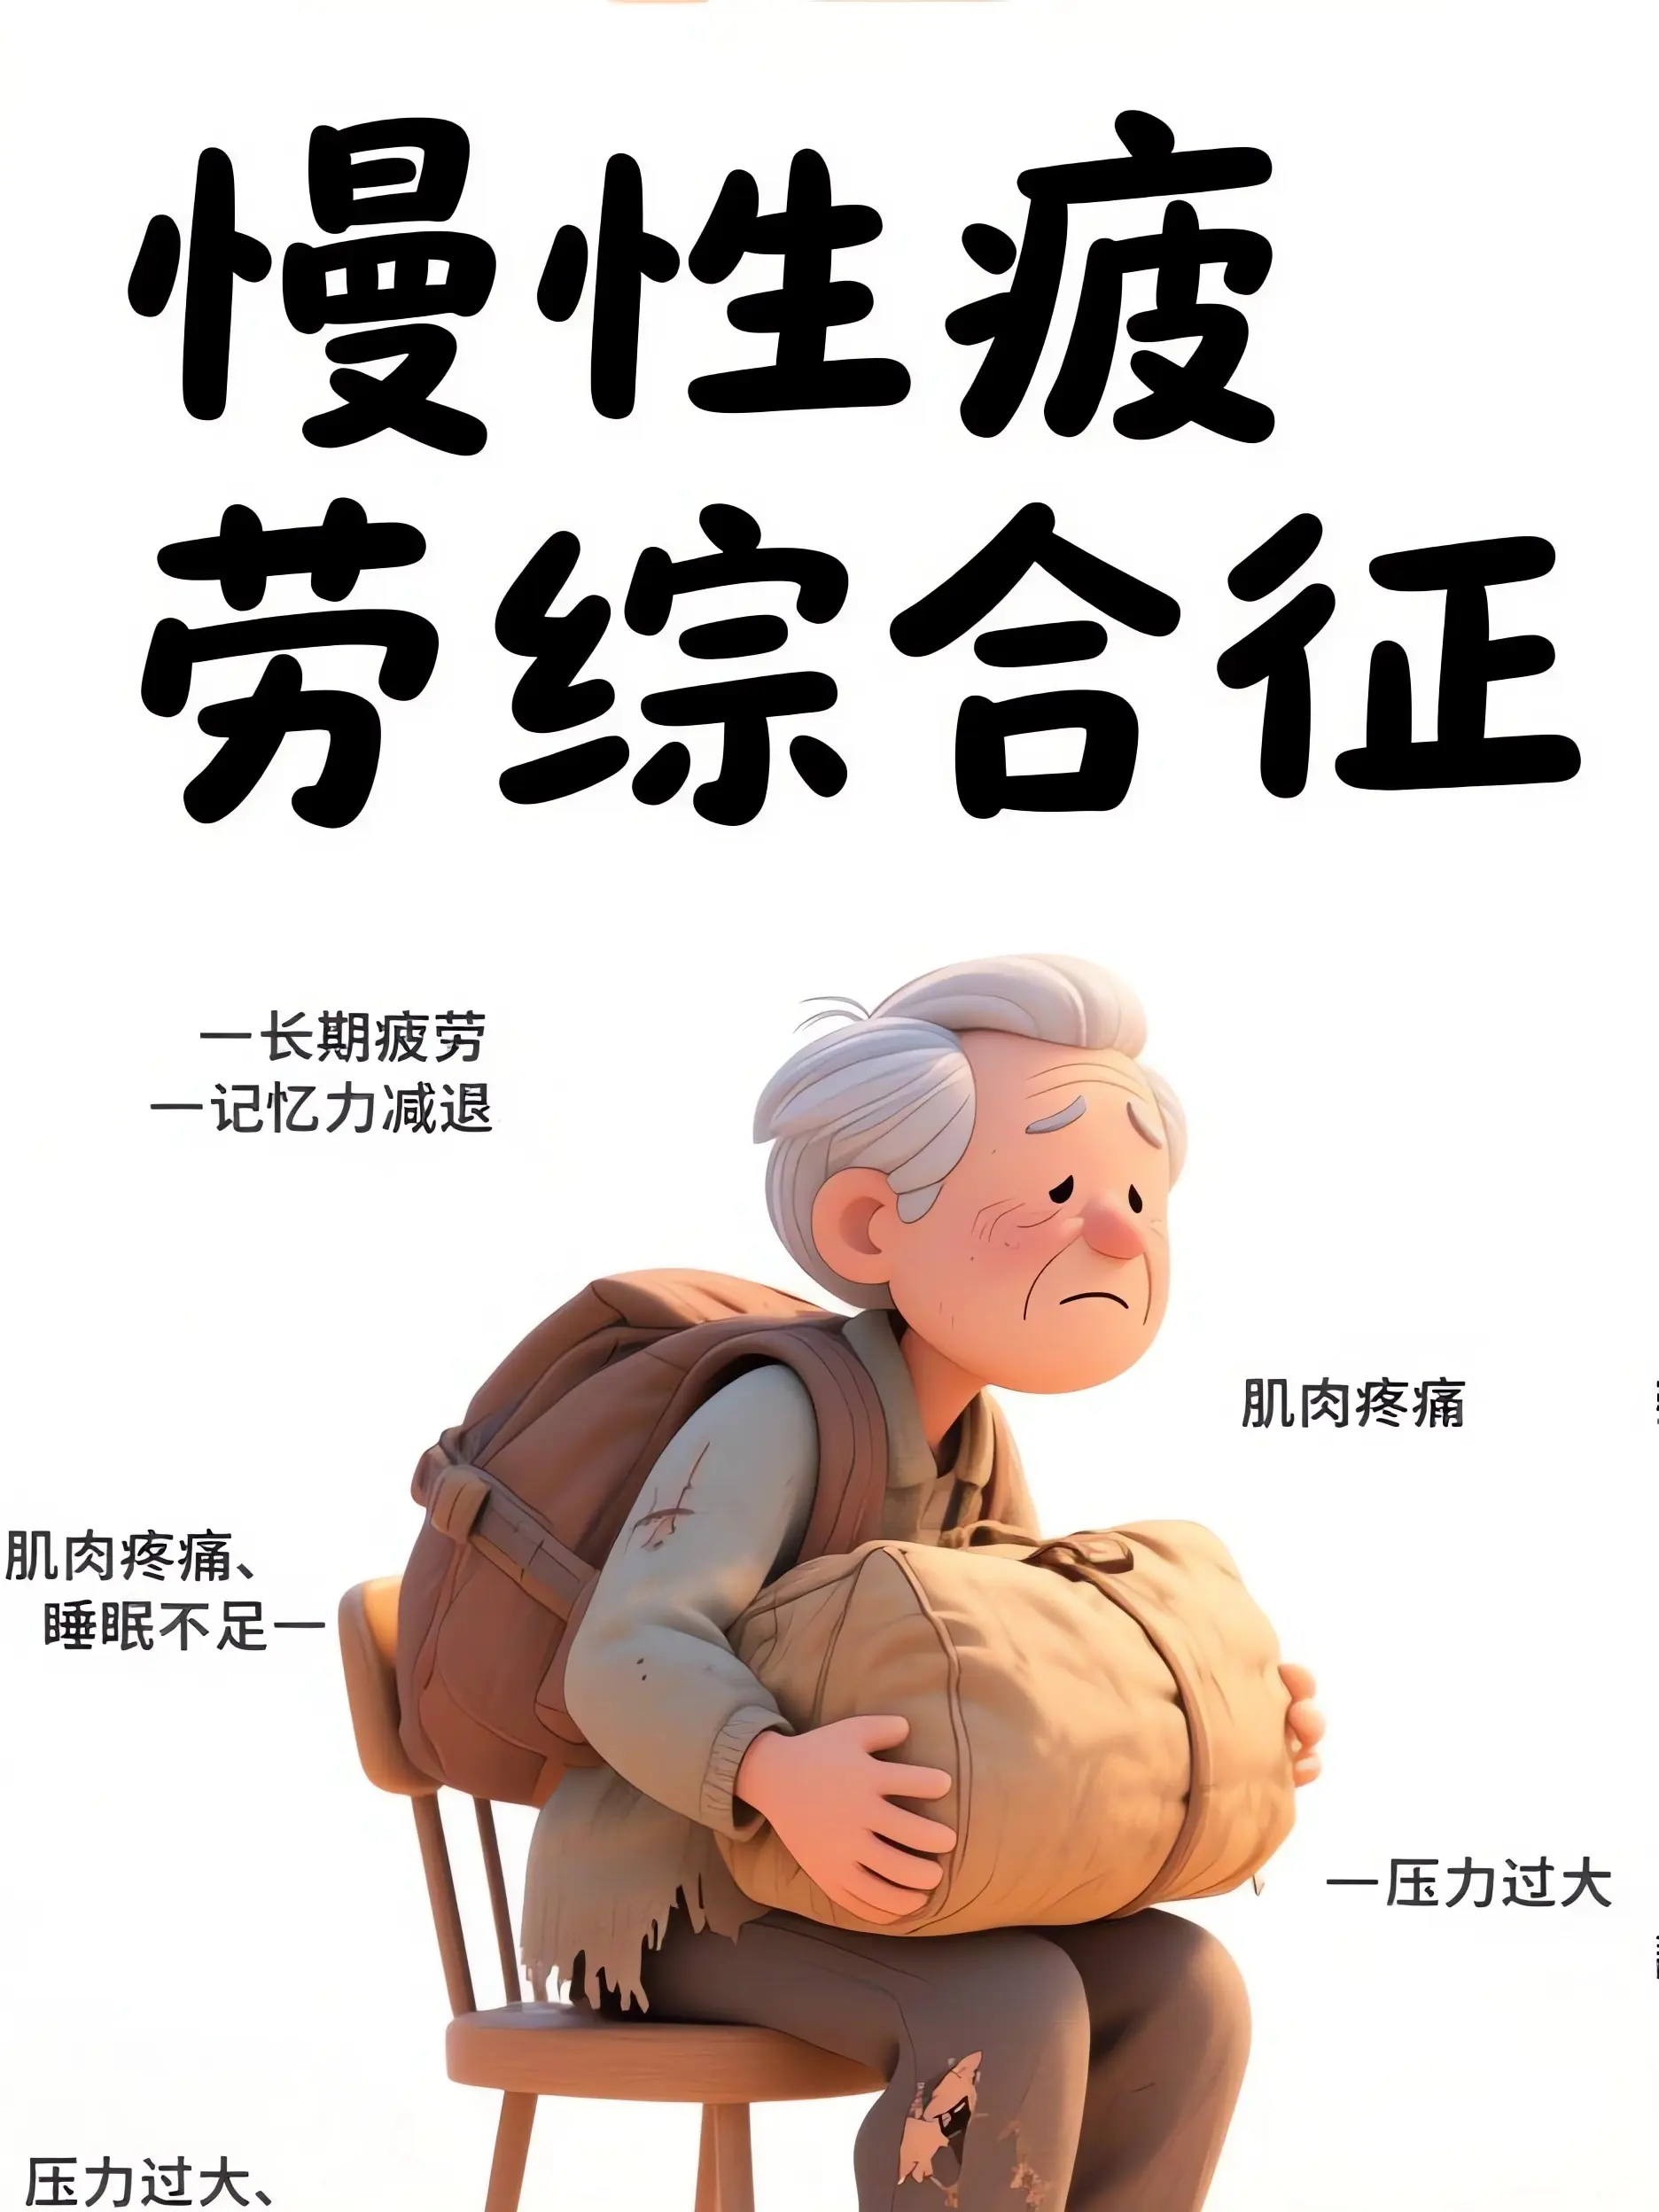

醫療宣傳知識科普...

269人浏覽中

醫療宣傳知識科普...

521人浏覽中